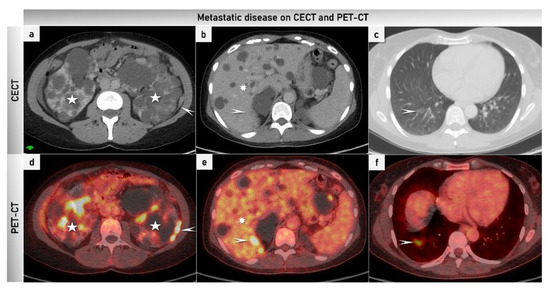

2.3.4. Positron Emission Tomography